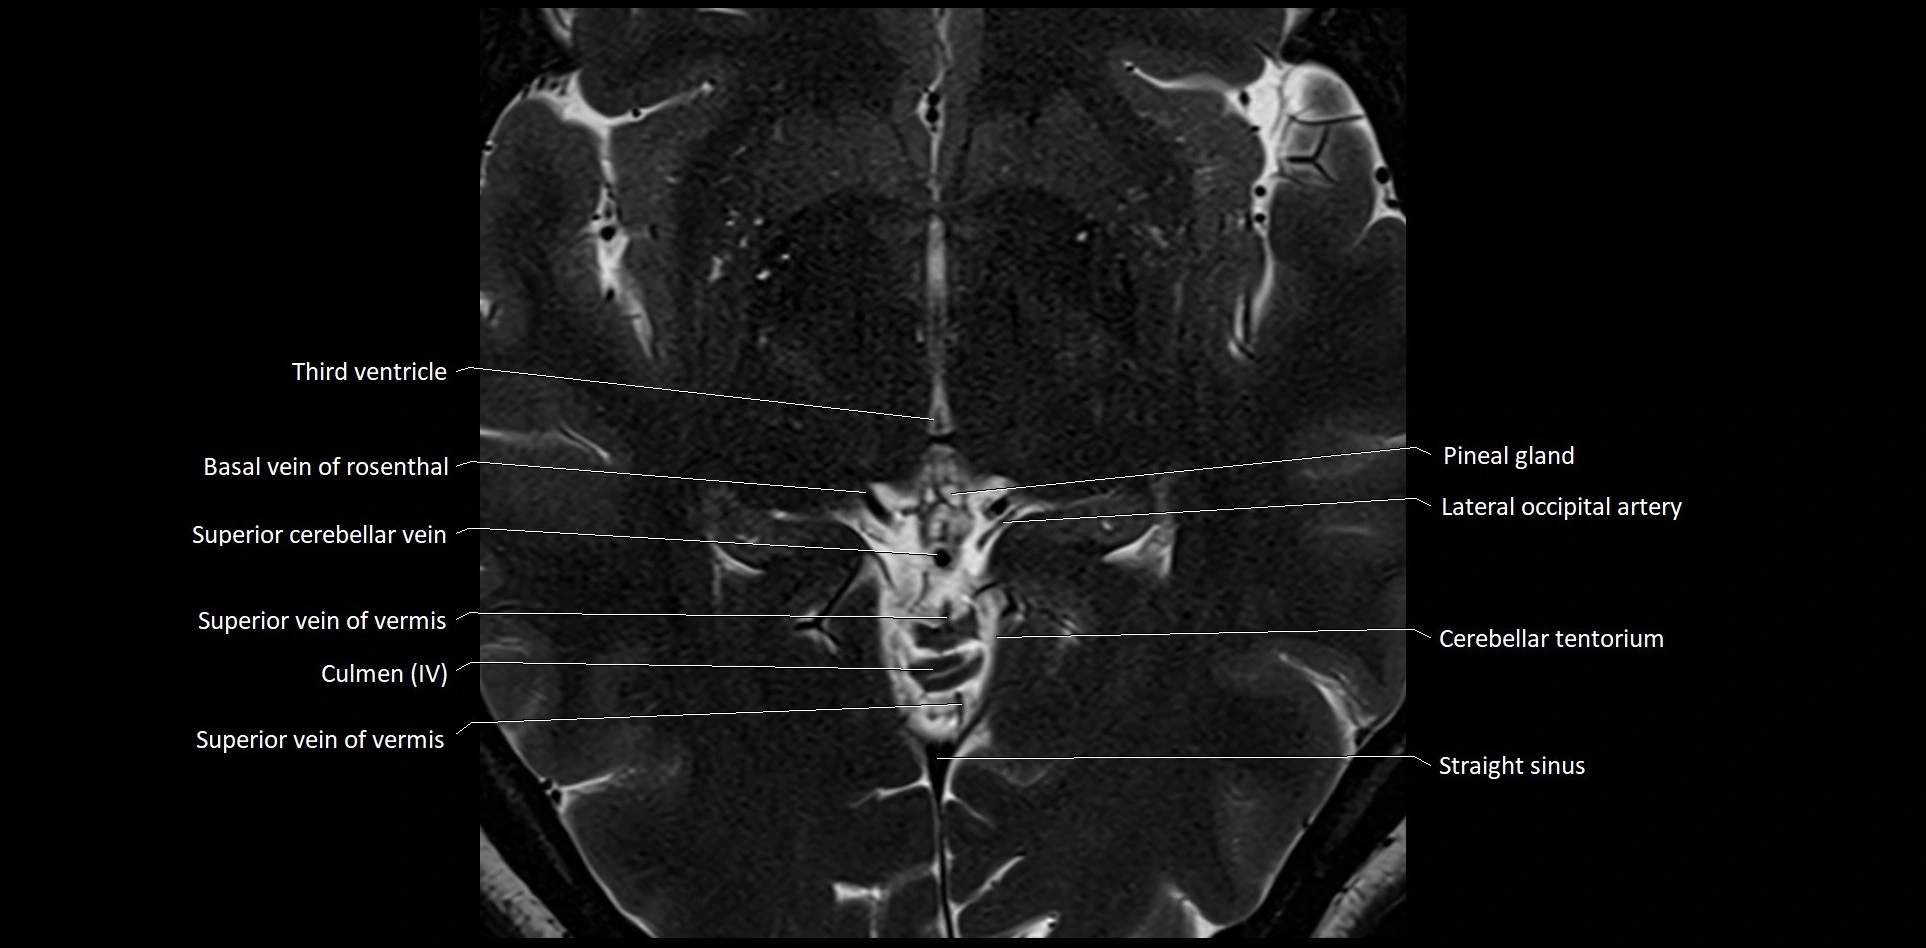

MRI images